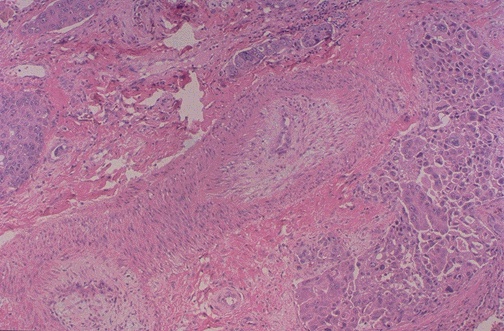

Image 3.4

The microscopic appearance of the lung is seen at low power.